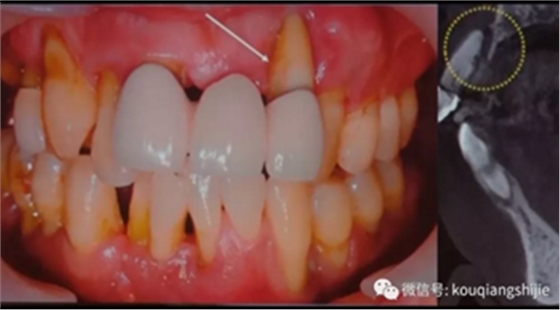

这是另一个患者

我们可以看到#23的颊侧骨壁基本已经破坏没了

从CT上我们也可以看到腭侧形成非常厚的黏膜

拔牙后我们可以看到这部位的骨缺损非常严重,需要大量的骨增量和黏膜增量。